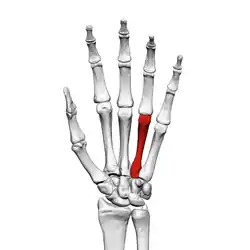

![]() Fourth metacarpal of the left hand (shown in red). Palmar view. | |

The fourth metacarpal bone (metacarpal bone of the ring finger) is shorter and smaller than the third.

The base is small and quadrilateral; its superior surface presents two facets, a large one medially for articulation with the hamate, and a small one laterally for the capitate.

On the radial side are two oval facets, for articulation with the third metacarpal; and on the ulnar side a single concave facet, for the fifth metacarpal.